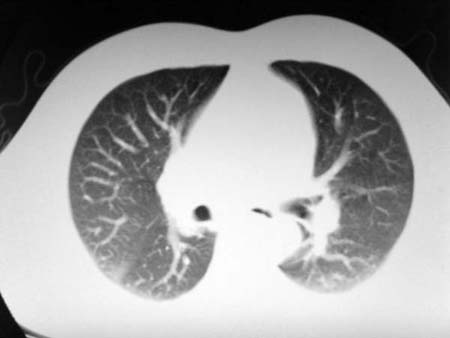

以下是引用qian在2008-4-27 17:02:00的发言:[br]考虑右下肺肺段隔离症伴有感染,建议做增强看看。

以下是引用zsl6918在2008-4-27 17:13:00的发言:[br]考虑右肺下叶炎性病变可能性大,建议抗炎治疗后复查,现有资料不能完全除外肺癌可能。